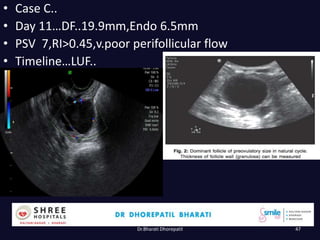

• Case C..

• Day 11…DF..19.9mm,Endo 6.5mm

• PSV 7,RI>0.45,v.poor perifollicular flow

• Timeline…LUF..